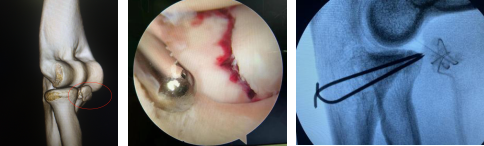

术前(左图)关节镜下(中图)术后即刻(右图)

关节内骨折的治疗要求较高,传统的手术治疗方式需要切开关节囊,破坏关节的正常结构,术后容易出现创伤性关节炎、关节不稳和关节僵硬等并发症。肘关节镜微创手术依次进行肘关节血肿的清理、骨折的复位,利用肘关节镜下复位、固定尺骨冠突骨折断端及桡骨头骨折。患者术后肘关节功能恢复良好,无疼痛及不稳,取得满意效果。